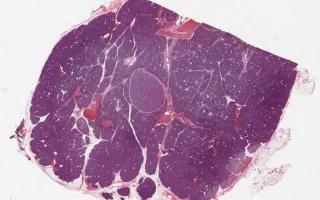

45 year-old female underwent a distal pancreatectomy for serous cystadenoma (not shown). This is an incidental finding in a representative section of grossly normal pancreas.

Pancreatic neuroendocrine tumours (NETs) are neoplasms of the endocrine pancreas, thought to arise from the cells of the islets of Langerhans. They show an equal incidence rate in males and females with an average age at diagnosis of 60 years. Pancreatic NETs can be associated with clinical signs and symptoms of hormone overproduction, such as insulin, glucagon, gastrin, and somatostatin; these are termed "syndromic NETs." The majority of pancreatic NETs are well differentiated and behave in a low grade manner. Features suggestive of a high grade lesion include larger size, higher proliferative index (either through mitotic rate or Ki-67 immunohistochemistry), and poorly differentiated morphology.

This case is an example of a low grade pancreatic NET which showed strong glucagon staining by immunohistochemistry (clinical status unknown).

This slide shows H&E stain. See Related Content for Glucagon immunohistochemistry.